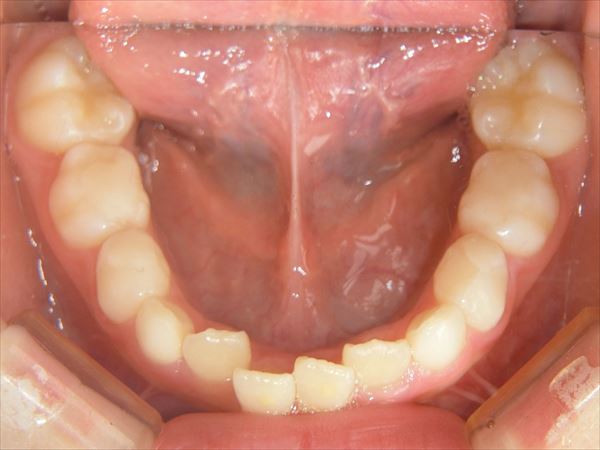

このような歯ならびを改善することができます。

プレオルソ (実際の症例)

症例1 でこぼこの歯並びを治したい

術前

叢生(でこぼこ)